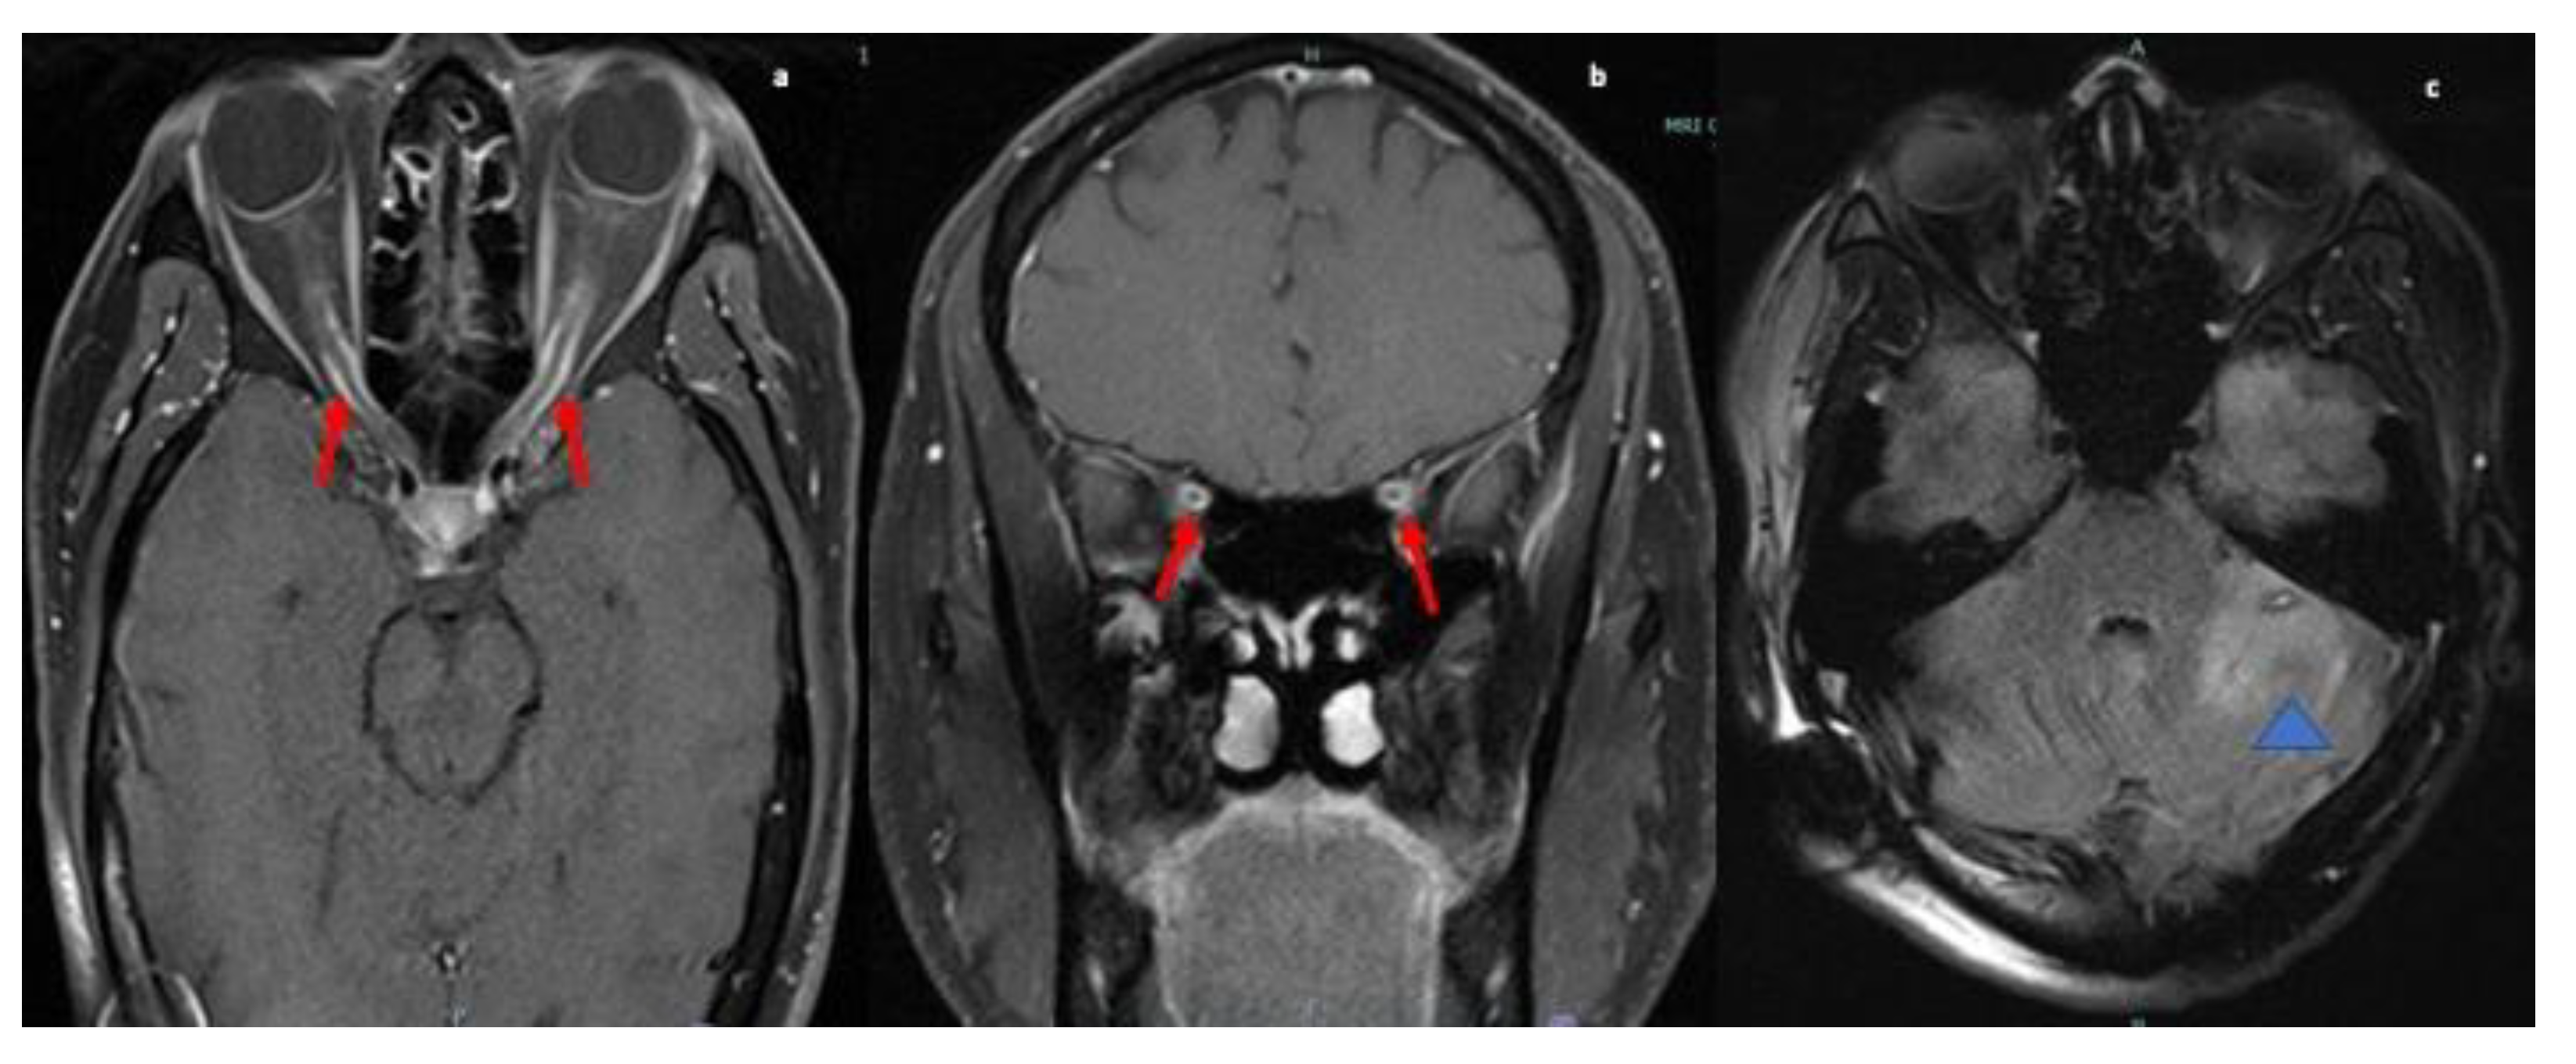

MRI brain showed abnormal enhancement within the right internal auditory canal with extension to the right cerebellopontine angle to the root of the VII and VIII cranial nerve complexes. MRI C-spine showed intramedullary enhancing lesions extending throughout the cervical spinal cord spanning C1 and C2. Multiple subtle foci of enhancement were also noted at C3 and within the lateral aspect of the medulla (refer to Figure 1). CT chest/abdomen/pelvis were without evidence of malignancy or systemic sarcoid.

Figure 1.

MRI sagittal T2 images (a) of the cervical spine reveal ill-defined long segment signal alteration with prominent cord expansion (red arrow) and ill-defined heterogenous lesion in cervicomedullary junction of the cord (blue asterisk); and (b) T1 post contrast image shows cord enhancement (blue arrow) and multiple separated subtle foci of enhancement were noted at C3 (yellow arrow). Axial T2-weighted (c) reveals corresponding hyperintense cord signal (blue arrowhead). MRI Brain sagittal and axial T1 post contrast images highlights homogenous enhancement at cervicomedullary junction (blue arrow; (d)), and enhancement along CN VII and VIII nerve complex (red arrow; (e)) & (blue arrowhead; (f)).

NS can affect the neurological system in various ways. One of these is cranial nerve involvement. Any of the cranial nerves can be involved in NS [11] but the most frequently reported is cranial nerve VII [1]. The first case in our series presented with lower motor neuron VII nerve palsy and VIII nerve involvement leading to a misdiagnosis of Bell’s palsy and ear infection. Multiple cranial nerve involvement, lesion within the brainstem and intramedullary lesions within the upper cervical spinal cord were seen on MRI were present in this case of NS. Despite treatment with steroids, the patient did not initially show improvement, complicating the case even further. The second case, initially diagnosed as orbital cellulitis, also demonstrated multiple cranial nerve involvement with ophthalmoplegia secondary to infiltration of the extraocular muscles due to granulomatous masses. The patient experienced loss of vision in the left eye due to surrounding inflammatory changes and mass effect. A subsequent biopsy confirmed the diagnosis of orbital sarcoidosis. Hence, cranial nerve involvement with other CNS lesions should raise suspicion for NS and treatment with steroids may not show a significant response initially.

Spinal cord predominant NS may involve leptomeningeal, pachymeningeal, and intramedullary regions, mimicking other myelopathies presenting with sensory, motor, and autonomic dysfunction [17,18,19]. Cervical and thoracic segment involvement is more commonly reported than lumbosacral involvement, similar to our case [19,20,21]. Junger et al. organized MRI manifestations ranging from Stage 1, indicating early inflammation to Stage 4, indicating progressive spinal cord atrophy [20].

Our first case presented with diffuse abnormal T2 signal throughout the cervical cord and intramedullary cervical cord enhancement with no cord atrophy consistent with stage 1 disease and involved more than three vertebral segments. In the past, authors have recommended using the length of spinal cord signal abnormality to aid in etiology of the lesions [14,17,18,19,20]. NS most commonly presents as multisegmental disease spanning multiple levels in the cord, uncommon in multiple sclerosis where plaques are usually shorter than two vertebral body lengths. However, longitudinally extensive spinal cord lesions (>3 vertebral segments on MRI examination) with acute myelitis are a characteristic feature of neuromyelitis optica spectrum disorders (NMOSD), which closely mimics NS, often leading to misdiagnosis [22,23]. Meningeal enhancement or persistent enhancement (more than a few weeks) of parenchymal lesions are much more suggestive of sarcoidosis than NMO [24]. Also, testing for the NMO/AQ-4 antibody is helpful in this setting, and was negative in our patient.